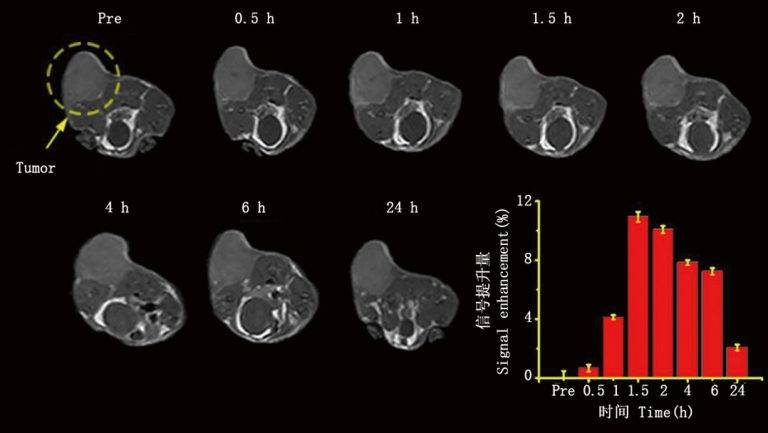

Subcutaneous tumour imaging

Small-animal MRI is a robust, non-invasive in vivo assessment tool for preclinical studies, drug discovery, and disease models. In preclinical workflows, in vivo MRI supports longitudinal studies to monitor disease onset, regression, and therapeutic response—non-invasively and without sacrificing animals at time points. The same animal can be imaged across multiple disease stages, reducing inter-subject variability.

Niumag’s compact small-animal MRI is an efficient imaging tool that rapidly delivers in vivo images in rats and mice. Compared with traditional anatomical methods, in vivo MRI requires no invasive procedures, avoiding secondary injury that could confound results. By imaging the same subject repeatedly, researchers obtain more accurate data on disease progression/regression, morphology, and quantitative parameters—greatly enriching study outcomes. Fast scan workflows further boost productivity. As a result, Niumag’s compact MRI has become an essential tool in the life sciences. With ongoing technology upgrades, it will continue to gain adoption and drive new insights and discoveries.